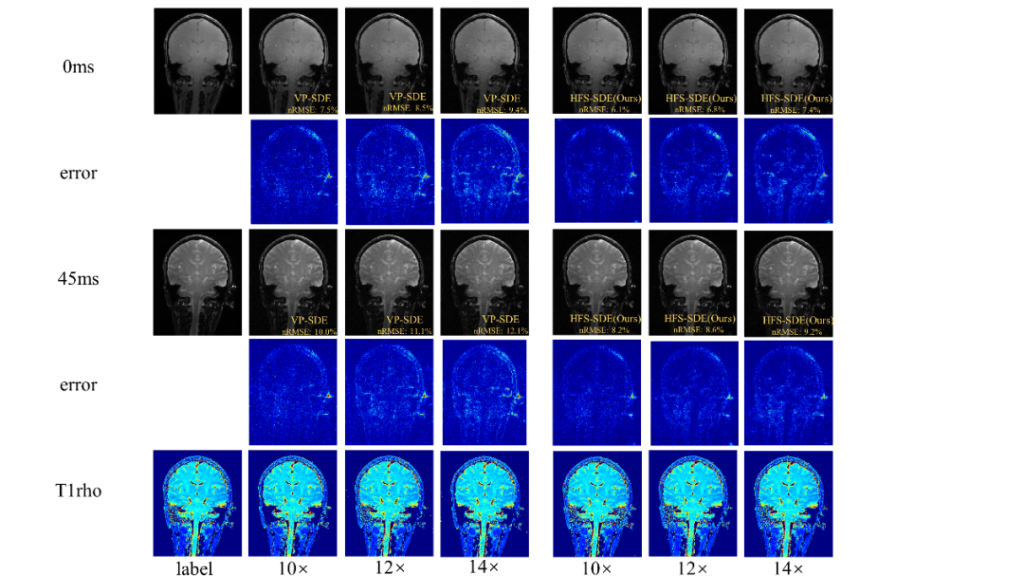

团队还提出一种用于基于扩散的MR重建方法——HFS-SDE,并将这种新方法应用于MR T1ρ映射,实现14倍的高加速度,相对于VP-SDE的高速倍数下没有显示伪影,nRMSE值明显优于VP-SDE,并且图像的高频细节得到了更好的重建。成果“Diffusion generative prior-based highly accelerated MR T1ρ mapping”在2023 ISMRM会议被收录为Power Pitch。

图4团队提出的HFS-SDE方法不仅提高了扩散模型的稳定性,并在5T时实现了T1ρ定量成像的高加速,而且更准确地恢复MR图像中的高频细节。